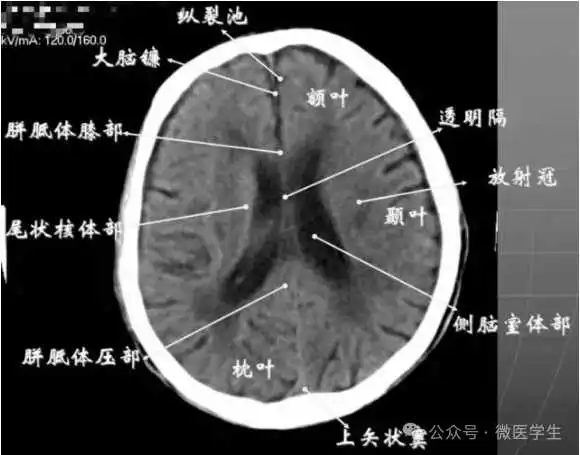

九面:听眦蝶鞍三下上体顶卵园灰质象1.听眦线层面(00mm)2.蝶鞍层面(+10mm)3.鞍上池层面(+20mm)4.三脑室下部层面(+30mm)5.三脑室上部层面(+40mm)6.侧脑室体部层面(+50mm)7.侧脑室顶部层面(+60mm)8.半卵圆中心层面(+70mm)9.灰质层面(+80mm)

由额、颞、枕叶构成,两侧侧脑室体部之间为透明隔,外侧为尾状核和体部。侧脑室后角(枕角)可不对称,室内可见脉络丛钙化。中线处可见大脑纵裂池和大脑镰。

内侧壁侧脑室体部被胼胝体分开,侧脑室体部的外方为顶叶,顶枕沟及中央沟将大脑为为额、顶、枕叶。

- 放射冠:是内囊到大脑皮质间的放射状纤维白质。